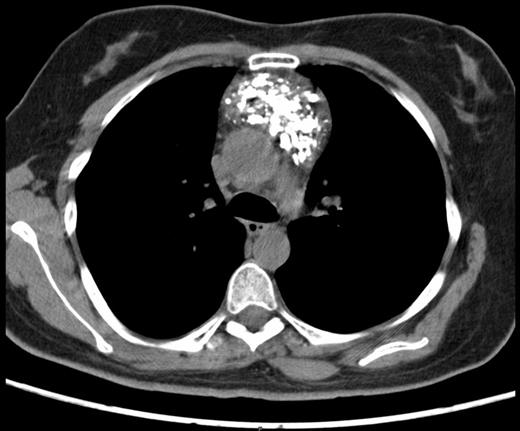

A 45-year-old female presented with symptoms of gastroesophageal reflux. Her past medical history included hypothyroidism and endometriosis. The patient reported fatigue over several months, but denied any chest pain, fever, dyspnea, cough or weight loss. Physical examination was unremarkable. She underwent a double-contrast upper GI series which revealed no abnormalities in the oesophagus or stomach but was suggestive of an intra-thoracic mass. Chest radiograph noted a heavily calcified mass in the anterior mediastinum. Computed tomography (CT) scan of the thorax revealed a well defined mass of mixed density with speckled calcifications located in the antero-superior mediastinum. The lesion extended from the sternal notch to the level of the aortic root (Figures 1a and 1b). Laboratory tests including β-HCG, α-fetoprotein, CEA, LDH and TSH were all within normal limits and pulmonary function tests were normal. Preoperatively, the working diagnosis was a thymoma, although not typical in appearance, and thus surgical resection was planned. The operation was performed through a median sternotomy. A radical “en-bloc” resection of the tumour, mediastinal fat, thymus, pericardium and pleura was carried out. There was no evidence of tumour dissemination in the pericardium or pleural cavities or metastatic lymphadenopathy. Macroscopically, the tumour was completely resected with negative margins. The patient had an uneventful postoperative course and was discharged one week after surgery. A 24 month follow-up has shown no recurrence of the disease.

Preoperative chest computed tomography scan revealing a large mediastinal mass - Axial view